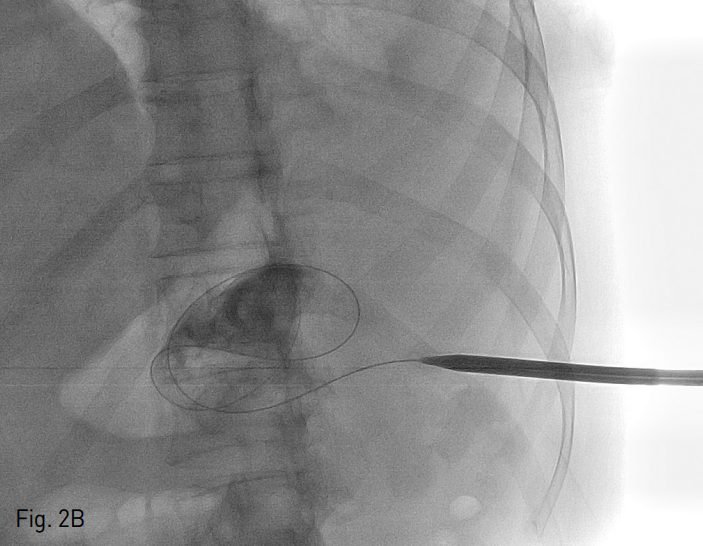

Fig. 2

Contrast accumulation through 5 Fr yellow sheath insertion after ultrasonograhy guided 22-gauge Chiba needle puncture (A). Up to 18 Fr rigid dilator was advanced coaxially over the 0.035 inch hydrophilic guide wire, progressively (B). 18 Fr Thal-Quick chest tube (Cook, Bloomington, IN, USA) was placed (C). The final catheter position can be confir med radiographically with contrast material (D).